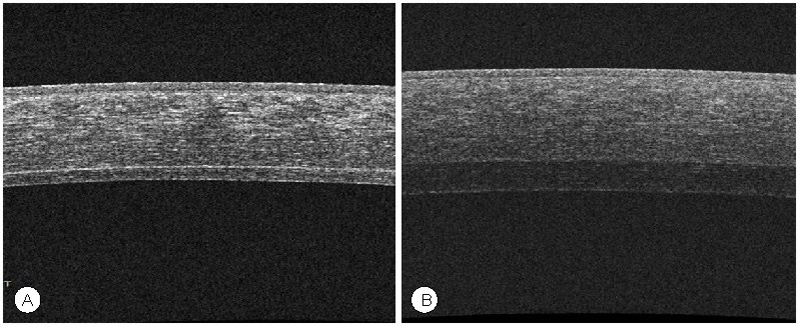

El tejido precortado ha cumplido las expectativas de la información técnica subministrada por el banco y solo en el caso del fallo endotelial primario parece tener alguna responsabilidad. Una vez implantadas las lamelas el grosor se ha corroborado mediante Tomografía de Coherencia óptica (OCT) (

Figura 15). El diámetro del área precortada es de 9 mm de diámetro o más en todos los casos. Por tanto se debe trepanar con un diámetro inferior para no incluir el borde y por tanto no obtener una lamela con un borde periférico de espesor completo.

Figura 15. OCT DSAEK vs Ultrathin DSAEK. Mediante el OCT spectral domain usado habitualmente en polo posterior somos capaces de discernir con detalle la interfase y el grosor de de la córnea donante y recptora. Apreciamos claramente que con los nuevos cabezales se obtienen lamelas posteriores de menos de 100µ (Figura 15a), mientras que en los primeros casos las lamelas tenían un grosor superior a las 150µ [(Fgura 15b).